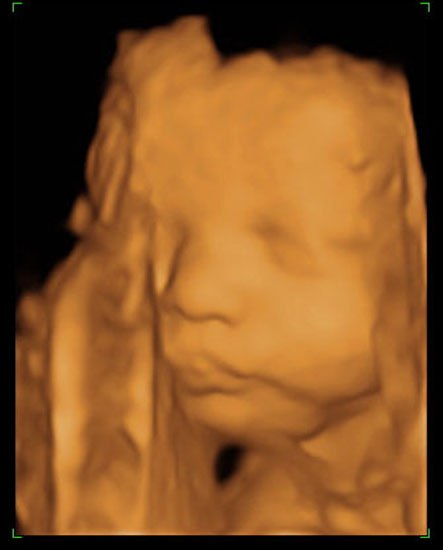

Pige2009

Jeg fik lavet 3D/4D scanning i 32. uge, og det var nærmest som at se den nyfødte baby. Vil klart anbefale dig at vente til du er længere henne

Bemærk at hendes storetå er mindre end de andre tæer - det har hun fra sin far

K.h. Linda